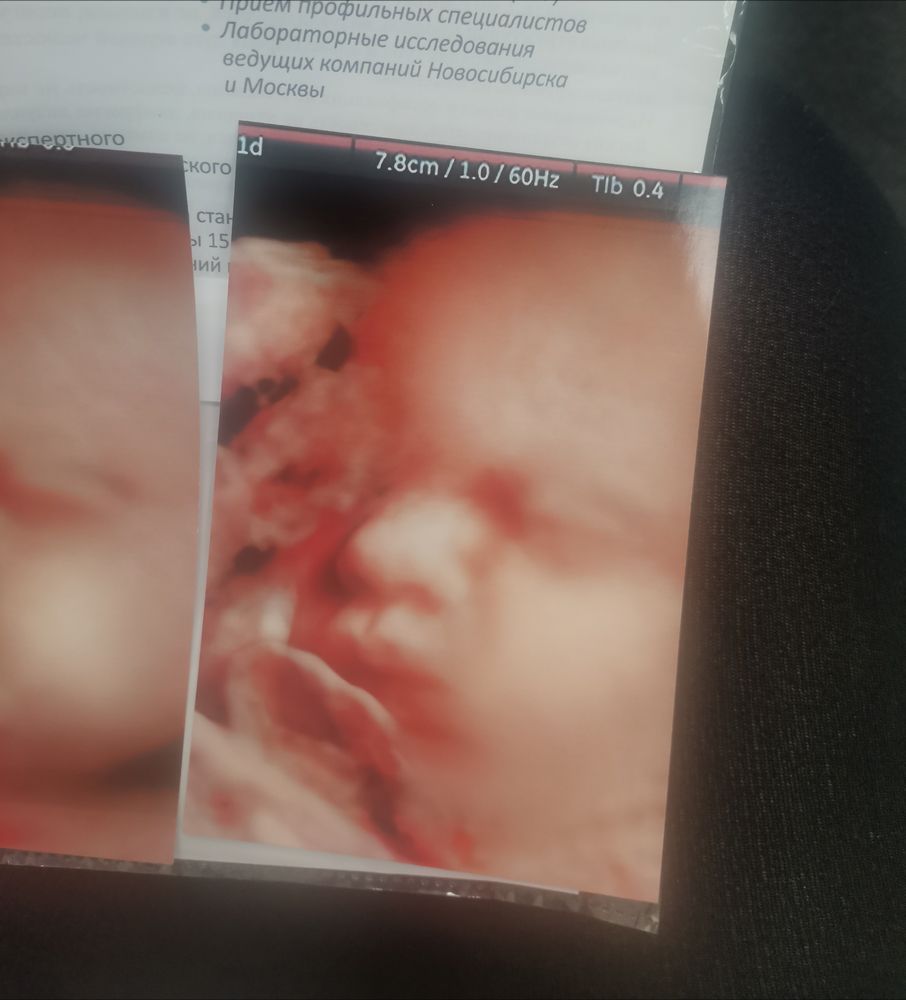

Сходила на 3 скрининг

С мальчиком моим всё хорошо, весит 1700.

Какое прекрасное узи - это же 3 d верно. Красивый мальчуган . Поздравляю вас . Хорошей беременности и родов вам легких